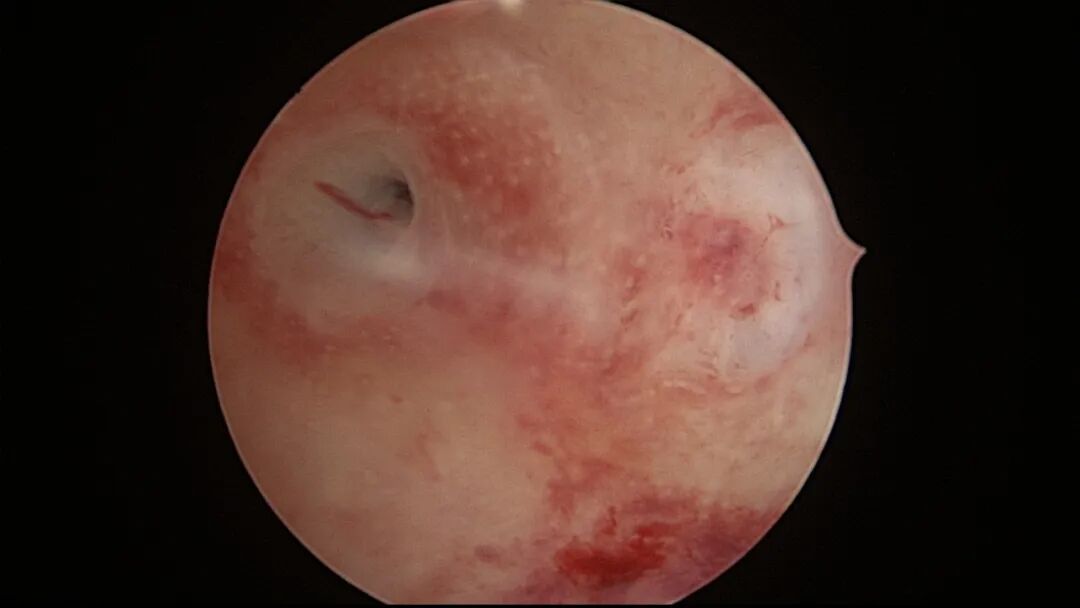

第四次宫腔镜:2021年10月宫腔镜二探取球囊,宫腔形态正常,右侧输卵管开口可见,左侧宫角见瘢痕,左侧输卵管开口隐约可见。